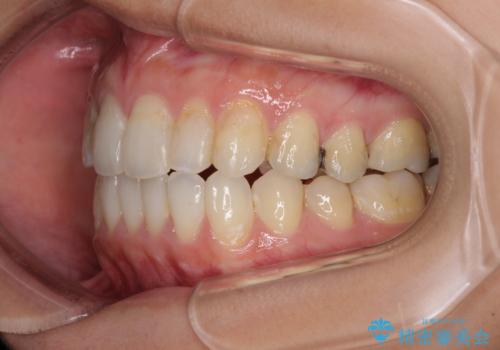

後戻りを治したい 骨格的なズレの大きい方のインビザライン矯正

- 中学生の時に矯正治療をしたものの、後戻りを気にして来院された患者様です。

骨格的に下顎が右側に変位しているため、左右の咬み合わせを理想的なものに改善することはできませんが、インビザラインにて歯列を整えることとしました。

骨格的なズレによる左右差は改善できませんでしたが、上下の正中を極力合わせるようにすることができました。